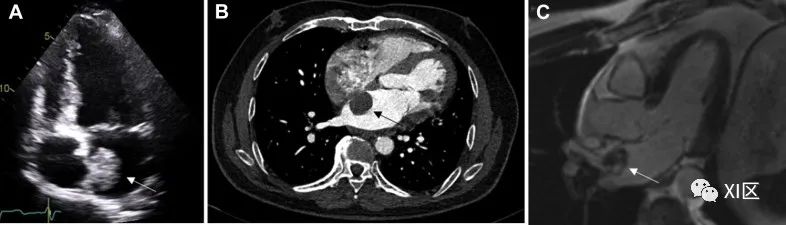

免疫功能正常患者的原发性心脏淋巴瘤(图 9)是一种不常见的恶性肿瘤,占 PCT 的 1.3%,而心外淋巴瘤的心脏转移则更为常见(约 25% 的淋巴瘤患者心脏受累)。几乎所有原发性心脏淋巴瘤都是侵袭性 B 细胞淋巴瘤,在艾滋病患者和接受过移植的患者中,继发于与 Epstein-Barr 病毒有关的淋巴组织增生性疾病的发病率越来越高。确诊时的平均年龄为 63 岁。最常累及心脏右侧,尤其是右心房,但任何心腔均可受累。病变常为多发。

图 9 原发性心脏淋巴瘤72 岁女性,原发性心脏淋巴瘤,表现为呼吸急促和外周水肿加重。(A)心脏肿块(白色箭头)在 CMR 上显示斑片状异质性晚期钆增强。(B)治疗前的 FDG PET/CT。肿块(白色箭头)内 FDG 摄取增加,取代了右心房并延伸至右心室。(C) 治疗后的FDG PET/CT 。右心房心脏肿块(白色箭头)完全代谢清除。

原发性心脏淋巴瘤的症状无特异性。可表现为心律紊乱,包括心脏传导阻滞、晕厥发作,甚至局限性心肌病。全身不适(发热、寒战、出汗和体重减轻)、胸痛和呼吸困难也很常见。约 20% 的患者可能在出现其他症状之前就出现急性心力衰竭。

在超声心动图上,这些肿瘤可表现为均匀的浸润性肿块,导致室壁增厚和限制性生理学改变,也可表现为侵入心腔的结节性肿块,好发于右心室(尤其是右心房)。房室沟也会受到影响,包绕右冠状动脉,心包也会出现渗出或包绕。心脏 CT 可显示大的局灶性肿块、弥漫性软组织浸润或多发结节伴异质强化。纵隔淋巴结病也可能出现。在 CMR 上,组织在 T1 加权成像上呈等信号,但有些病例报告有低信号病变。在T2加权成像上,病灶因弥漫性水肿而轻度高信号。也可观察到提示中心坏死的散在低信号区。18F-FDG PET 通过 18F-FDG 的摄取强度提供病变中细胞代谢和增殖程度的信息,18F-FDG 的摄取强度与病变的恶性程度成正比。18F-FDG PET 还可在化疗结束后进行,以评估最终的治疗反应。